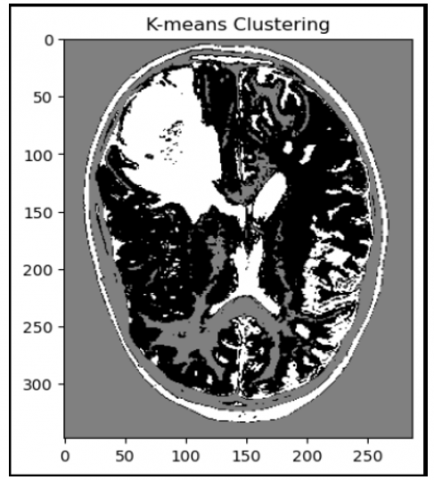

Algorithm k-means clustering

Step 1: Import important libraries like numpy, cv2, K-Means clustering.

Step 2: Load the MRI image.

Step 3: Preprocess the image through resizing and flattening which is necessary for k-means clustering.

Step 4: Train k-means clustering algorithm with n_clusters = 3. This will group similar pixels into 3 clusters.

Step 5: Visualize the new labels into a segmented image.

Figure 3 shows the results of using K-means clustering to segment highlight the brain tumor.

Figure 3. Result of k-means clustering program for segmentation